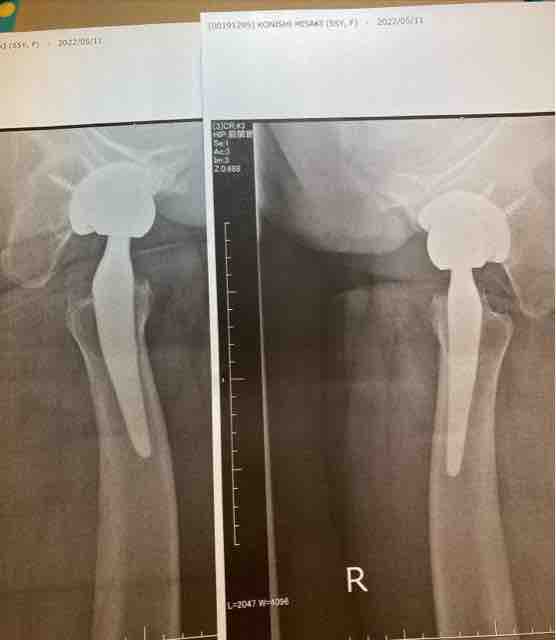

Dr.¡Ö¥ì¥ó¥È¥²¥ó¤Ç¤ß¤Æ¤âåºÎï¤ËÆþ¤Ã¤Æ¤¤¤ë¤·¼ê½Ñ¸å¡¢£¶¥õ·î¸¡¿Ç¤ÈÈæ¤Ù¤Æ¤âÁ´¤¯ÌäÂê¤Ê¤¤¤Ç¤¹¤è¡£¡×